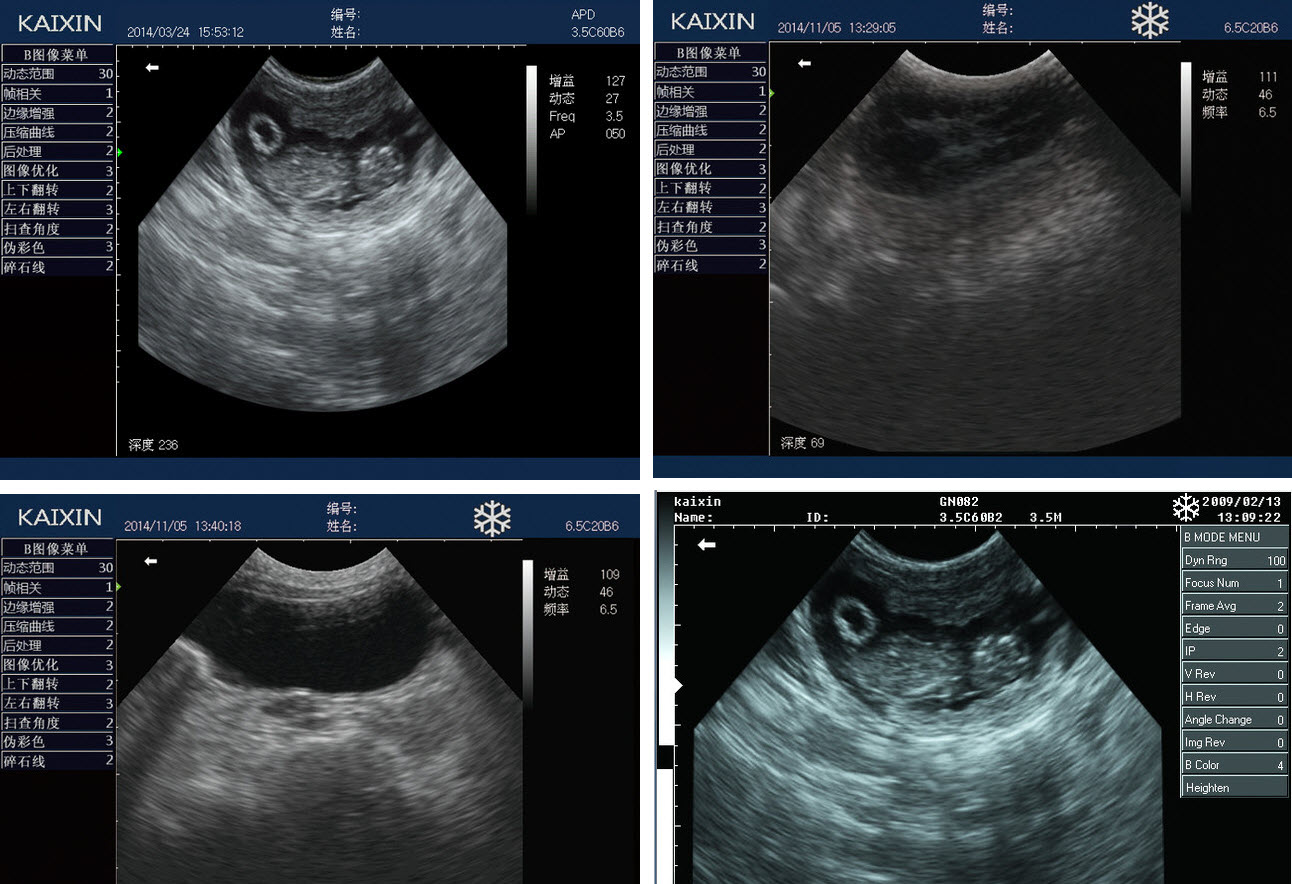

Приклади зображень УЗД апарату KX5600